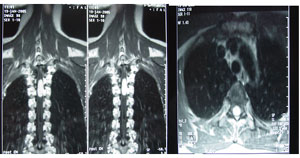

X線平片檢查約有30%~40%的患者可見骨質改變,在常規的脊柱正側位片及斜位片上,常見的徵象有:(1)椎間孔擴大或破壞;(2)椎管擴大,表現為椎弓根間距增寬;(3)椎體及附屬檔案的骨質改變,可見椎體骨質缺損、椎弓根破壞等;(4)椎管內鈣化,偶見於少數脊膜瘤,畸胎瘤及血管母細胞瘤;(5)椎旁軟組織陰影。由於椎管內腫瘤多為良性,早期X線片上常無骨質異常表現,有時僅在晚期可見椎弓根間距增寬,椎管壁皮質骨變薄椎管擴大等間接徵象。對於啞鈴形椎等內腫瘤,可見椎間孔擴大。X線片檢查,可排除脊柱畸形、腫瘤等原因造成的脊髓壓迫症,仍為一種不可缺少的常規檢查。

症狀輕或自發性緩解的患者可以保守治療,並予反覆、多次體檢和MRI複查(注意:有復發和脊髓損傷出血的危險)。但是,唯一有效的治療是手術切除腫瘤,由於原發性椎管內腫瘤以良性居中,約3/4病例可以手術切除治癒因此,對椎管內腫瘤應力爭手術切除,即使不能完整切除,也應行部份或大塊切除,以減輕或緩解腫瘤對脊髓的壓迫和損害。一旦明確診斷,應積極創造手術條件,不論脊髓受壓程度的輕重,均應及時手術治療。手術有風險,症狀可反覆手術風險依其所處功能位置而不同,外生性者術後缺陷少。應選擇合適的治療手段。術中脊髓誘發電位監護有助於減少神經併發症。